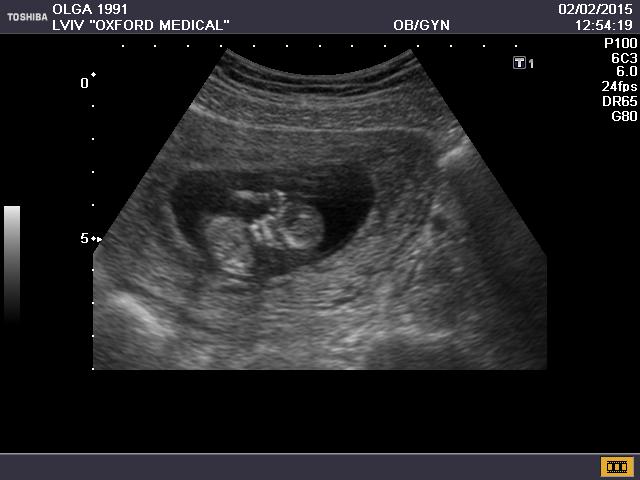

Первый скрининг) 12 недель)

Мои неделькиСегодня были на узи с мужем, он первый раз увидел малявку,жаль не сфоткала его выражения лица)))) Первой фразой было "он там так прыгает,как ты не чувствуешь?")))))Я то уже неделю назад виделась с крохой(непонятно зачем врач не предупредила что на скрининг надо будет делать еще узи, я ы не делал 2 подрят). На этот раз врач предположила нам мальчика( делала узи другой врач). Будет папин сыночек, все личиком поворачивался и махал ручкой папе, ко мне попкой поворачивался прошлый раз))))Но я не в обиде)) По показателям все у нас тьфу-тьфу хорошо) Завтра сдаю кровь))Вот так малыш передает привет